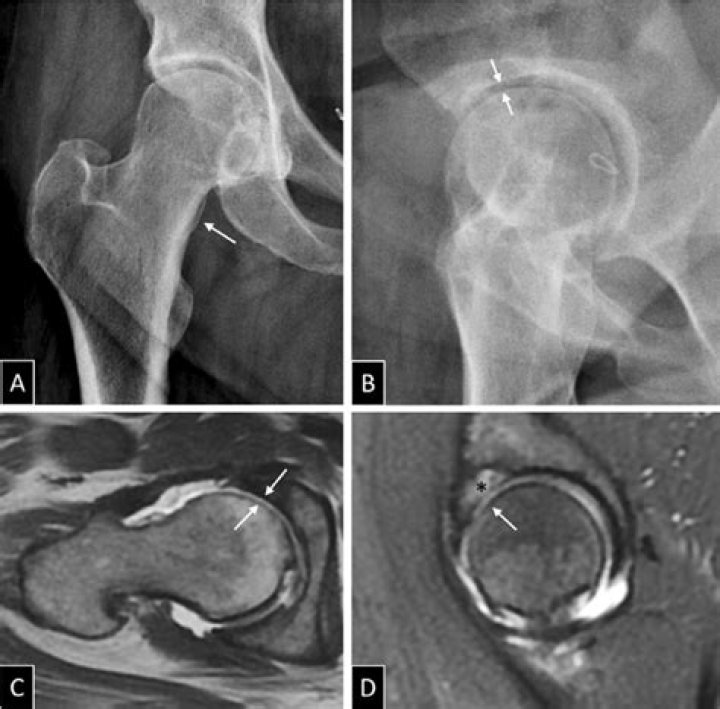

Arthrography involves placement of a needle intra-articularly with aspiration of joint fluid and injection of a contrast agent to enhance imaging. It is often performed to exclude an infection in patients with hip pain or in patients with total joint prostheses.

An arthrogram is a test that helps healthcare providers diagnose joint problems, such as hip or shoulder pain. MR arthrograms can show ligament, tendon and cartilage issues with clear detail. You get a special dye injected into your joint before having an MRI scan or other imaging test.

A posteroinferior sublabral groove is a relatively common normal anatomic hip variation. If not recognized as normal, the sulcus may serve as a diagnostic pitfall on MR arthrography. Its location is distinct from most labral tears.